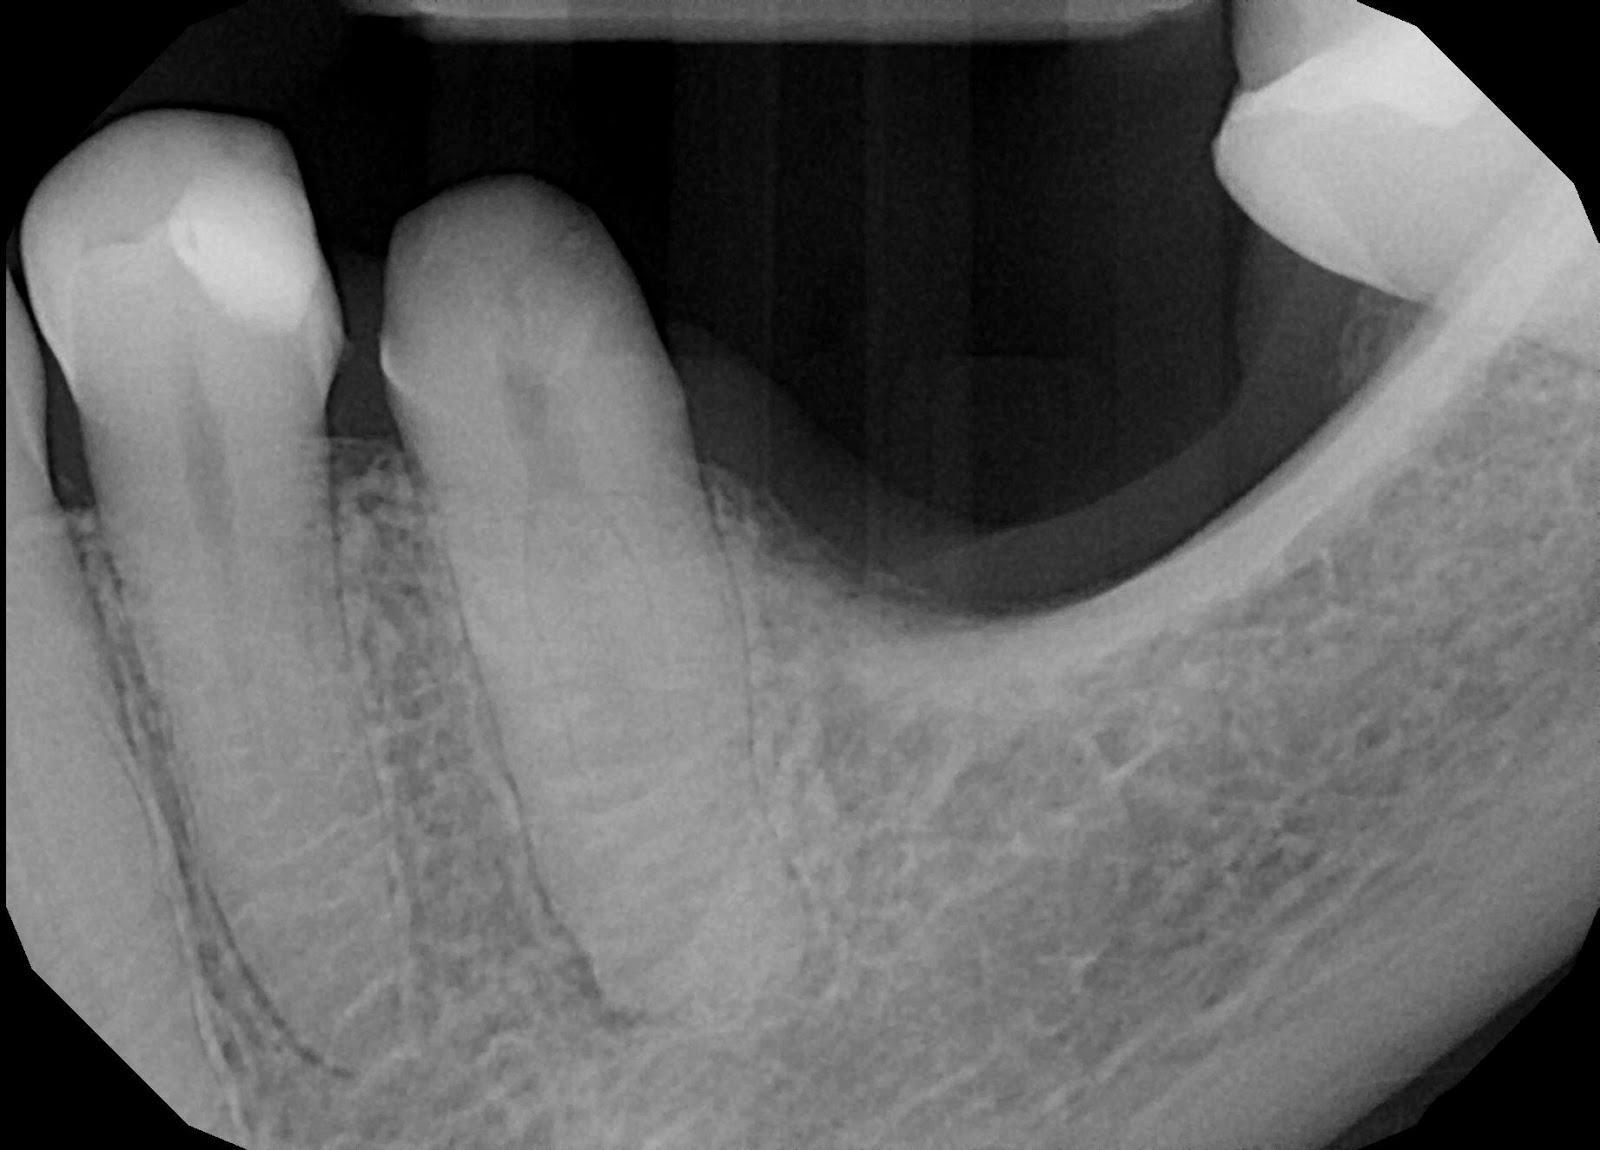

Above in the picture on the left is a tooth that has been prepared for a crown. All the decay the tooth had was removed and then a base of tooth was made from enamel colored filling material. Above on the right is an x-ray showing the buildup fully restored with the crown in place.